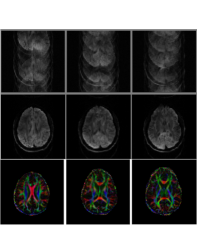

VIII-B1 Correction of phase errors in multi-shot diffusion MRI [18]

Diffusion MRI (DMRI) is a valuable tool for assessing brain connectivity and tissue micro-structure. High-resolution DMRI is often acquired using multi-shot EPI schemes, where different Fourier regions are acquired from different radio-frequency excitation pulses. For example, the even lines in a two-shot EPI sequence are collected from one shot, while the odd lines are collected in the second shot. Subtle physiological motion between the shots in the presence of diffusion encoding gradients manifest as motion induced phase errors between the shots. Previous works [18] have shown that these phase errors can be corrected using the SLR scheme, even when the data is acquired using 4-8 shots. The results in Fig. 6.(a) shows the improved reconstructions offered by this scheme.